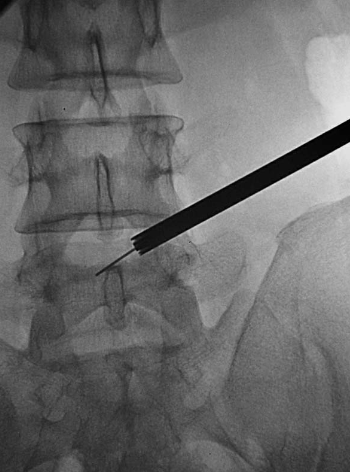

置入1级导杆:使头端到达第一靶点(图15)。

图15 置入1级导杆A.前后位透视头端到达第一靶点;B.侧位透视头端抵达L5椎体后上缘。

依次置入1~3级扩张管扩张软组织通道,3级扩张管在椎间孔外受阻(图16)。

图16 依次置入1级~3级扩张管,扩张软组织通道,3级扩张管在椎间孔外受阻。

第一靶点成形:在导丝、1级导杆、1级扩张管与3级扩张管间,逆时针旋入1级环锯,进行1级扩孔环锯头端扺达第一靶点(图17)。

图17 第一靶点成形:前后位透视环锯头端抵达第一靶点。